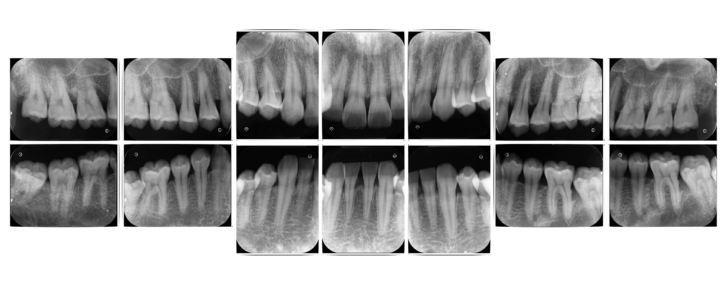

歯周組織検査のためのX線14枚法

⇩

下記に10年前に行った再生療法の症例をご紹介します。

失った骨の形態や噛み合わせなどにより、全ての患者様に再生療法が適応できる訳ではないですが、現在では症例や材料により保険適応ができる症例もございます。